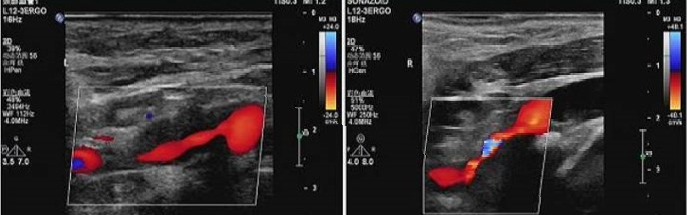

超声及超声造影

-- 左侧颈内不规则低回声,新生血管分级:IV级,提示为易损斑块

-- 右侧颈内不规则混合回声,表面钙化为主,新生血管分级:III级